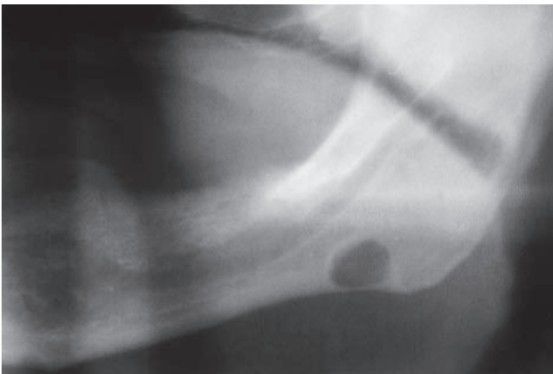

Static bone cyst

Represents lingual depression of mandible; filled with salivary gland or other soft tissue from floor of mouth; asymptomatic; an incidental finding that requires no biopsy or treatment.